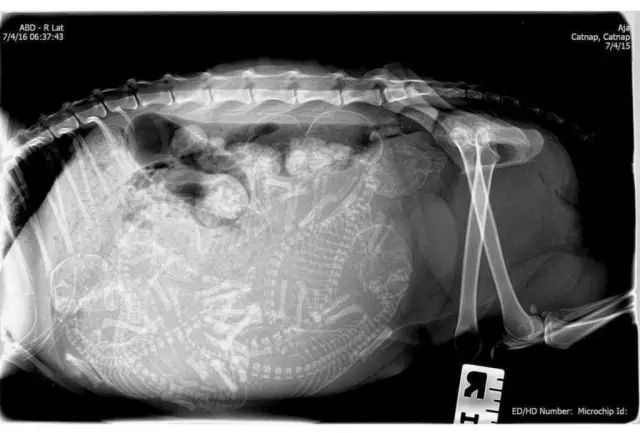

1. 狗狗。

能数得出是几胞胎吗?